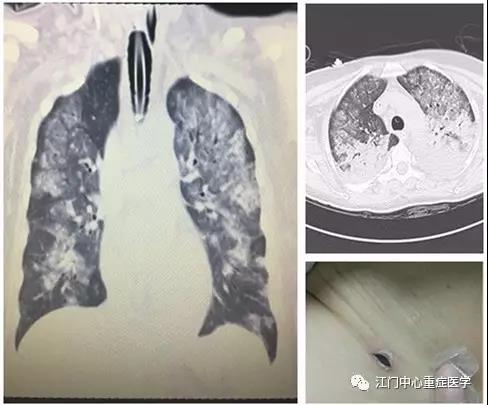

拔除气管插管后不久,婆婆的病情出现反复,很快再次出现呼吸困难,千钧一发之际,医生再次为婆婆气管插管。经过二次打击,婆婆脆弱的心肺也再陷入了旋涡,检查发现她的心包积液、胸腔积液量增多,右心室被明显压迫,左下肺实变。为降低穿刺引流风险和提高拔管成功率,重症医学科医疗小组发挥多学科综合治疗(MDT)的优势,联系超声介入科帮婆婆穿刺引出心包及胸腔积液。